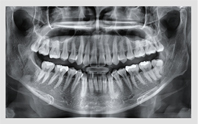

• 3D CT

치아, 잇몸뼈 골격까지 진단

• 정밀한 진단을 통한 체계적인 계획

치아뿌리 길이, 모양, 잇몸뼈의 두께와 밀도, 과잉치와 치아종 등 3D CT 정밀진단을 통해 환자의 치아 및 잇몸 상태를 고려한 치료계획을 세울 수 있습니다.